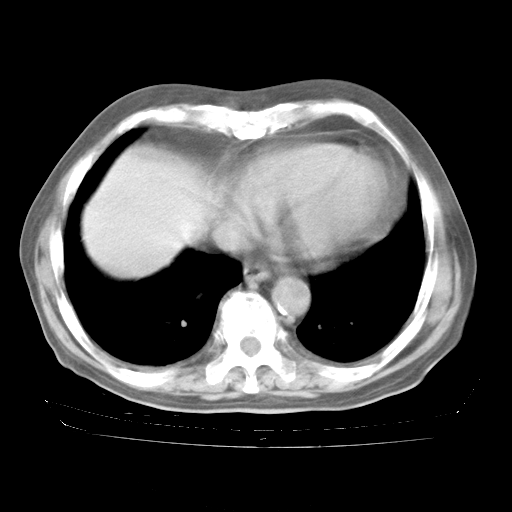

4月28日肺部CT——再次出现类似去年5月9日——透光度降低,“间质性”改变。

4月28日肺部CT——再次出现类似去年5月9日——磨玻璃样、间有“粟粒样”改变。

4月28日肺部CT